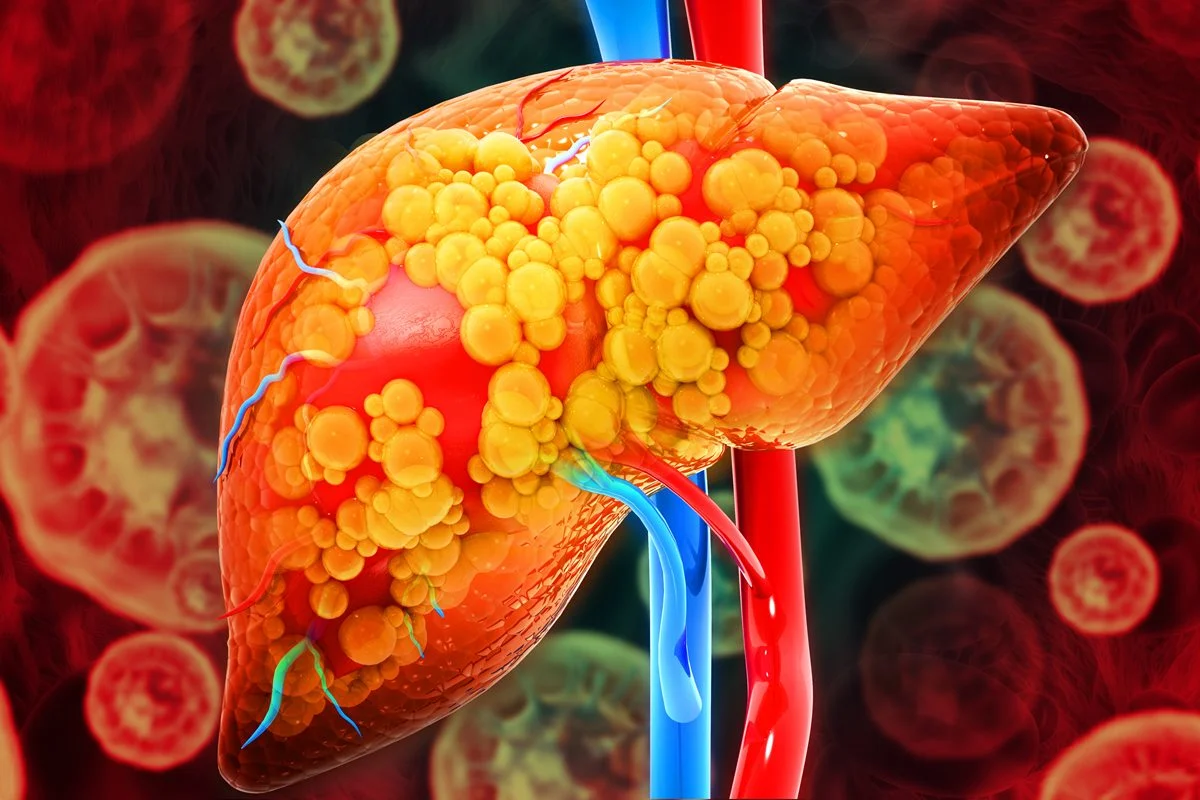

A esteatose hepática é popularmente conhecida como gordura no fígado

A condição de gordura no fígado acomete 30% da população mundial